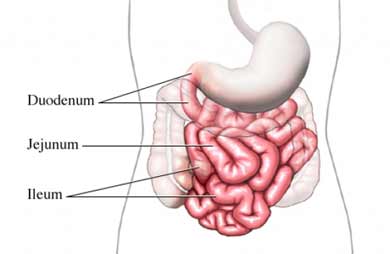

This weekend was my first at home after two weeks in the hospital and I feel like crying with gratitude for having had it and I feel very afraid about needing to go back since, after 14 days, the blood leak that caused my anemia wasn’t found, never mind treated. The only thing I came home with that I didn’t have when I left was a surgical wound on my belly. It’s grotesque. I’m also afraid of the anemia returning. The last time I had it, the incident that provoked the hospital visit, I didn’t have the strength necessary to get off the bed. I went to the emergency clinic by ambulance. The worse things about being in the hospital are the loss of autonomy, the pain of the many, many needles you must endure, nurses and doctors are free to come and go at any moment and the ugliness of your surroundings. When I arrived home, the bed was covered by a duvet we had just bought, kind of a deep Mandarin red with gold paisley, and it looked so comforting and inviting and big, big enough to lie down next to my wife, which reminds me of something of another effect of the hospital – the loneliness, because even if you are, like me, lucky enough to have your best friends and closest relatives visiting you at all hours, they’re leaving and you cannot leave with them and just that fact reminds you of your isolation. All you seem to talk about is your illness, which is really all you’re thinking about because, what else is there, and that makes the visit bittersweet. So does the knowledge that they’re there for you, to help take care of you and you hate to do that to them. Or you’re thinking about food, where will the next meal come from or even whether you’ll be allowed a next meal, since, for the bulk of my time there I was limited to clear liquids. I would eat the hospital’s jello and Jolean would go down to The Pastrami Queen and bring back quarts of chicken soup. Missing your wife at night and knowing that, when she arrives, you will have a list of foraging for her (which she will cheerfully take care of) as opposed to home, where you can hold her and love her and for a while forget that you’re the one being taken care of. All your stuff is home and the anchoring quality of being among your stuff is not to be undervalued. There’s my guitar. There is a pile of books. There is the footboard of the big brass bed.

This weekend was my first at home after two weeks in the hospital and I feel like crying with gratitude for having had it and I feel very afraid about needing to go back since, after 14 days, the blood leak that caused my anemia wasn’t found, never mind treated. The only thing I came home with that I didn’t have when I left was a surgical wound on my belly. It’s grotesque. I’m also afraid of the anemia returning. The last time I had it, the incident that provoked the hospital visit, I didn’t have the strength necessary to get off the bed. I went to the emergency clinic by ambulance. The worse things about being in the hospital are the loss of autonomy, the pain of the many, many needles you must endure, nurses and doctors are free to come and go at any moment and the ugliness of your surroundings. When I arrived home, the bed was covered by a duvet we had just bought, kind of a deep Mandarin red with gold paisley, and it looked so comforting and inviting and big, big enough to lie down next to my wife, which reminds me of something of another effect of the hospital – the loneliness, because even if you are, like me, lucky enough to have your best friends and closest relatives visiting you at all hours, they’re leaving and you cannot leave with them and just that fact reminds you of your isolation. All you seem to talk about is your illness, which is really all you’re thinking about because, what else is there, and that makes the visit bittersweet. So does the knowledge that they’re there for you, to help take care of you and you hate to do that to them. Or you’re thinking about food, where will the next meal come from or even whether you’ll be allowed a next meal, since, for the bulk of my time there I was limited to clear liquids. I would eat the hospital’s jello and Jolean would go down to The Pastrami Queen and bring back quarts of chicken soup. Missing your wife at night and knowing that, when she arrives, you will have a list of foraging for her (which she will cheerfully take care of) as opposed to home, where you can hold her and love her and for a while forget that you’re the one being taken care of. All your stuff is home and the anchoring quality of being among your stuff is not to be undervalued. There’s my guitar. There is a pile of books. There is the footboard of the big brass bed.